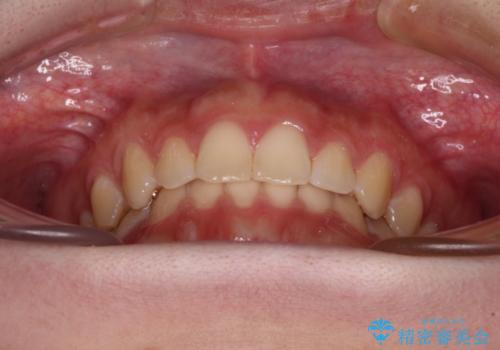

前歯のすきっ歯を治したい インビザラインによる矯正治療

- 上顎前歯の隙間を気にして来院された患者様です。

目立たない装置を希望とのことで、インビザラインを用いて矯正治療を行うこととしました。

最終的には隙間は全て閉じ、綺麗な仕上がりとなりました。